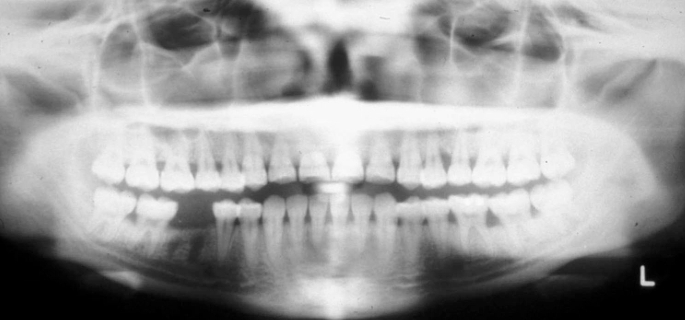

What is wrong with this image?

glasses